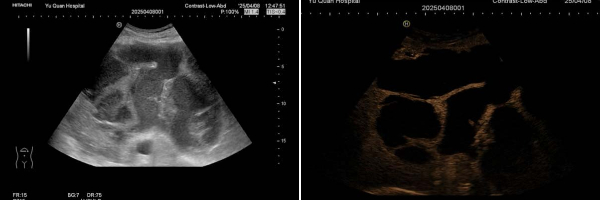

影像檢查陷困境 超聲造影“一錘定音”

該患者因在外院發(fā)現(xiàn)肝臟占位入住我院普外科。入院時(shí)腹脹、無腹痛、發(fā)熱。增強(qiáng)CT和增強(qiáng)MRI均提示肝臟巨大囊實(shí)性占位,但無法明確病變性質(zhì)。入院后完善相關(guān)化驗(yàn)檢查:白細(xì)胞15.76×*10^9/L,中性粒細(xì)胞計(jì)數(shù)13.84×*10^9/L,C反應(yīng)蛋白128.0mg/L,葡萄糖7.83mmol/L,腫瘤標(biāo)志物(-),患者有糖尿病病史且血糖控制不佳,且入院后已出現(xiàn)發(fā)熱癥狀,考慮肝膿腫可能。普外科請(qǐng)超聲醫(yī)學(xué)科會(huì)診:常規(guī)超聲探查肝左葉可見一囊實(shí)性包塊,大小約19.9x14.2x15.5cm。即刻行超聲造影檢查,實(shí)時(shí)動(dòng)態(tài)觀察該病灶的血流灌注方式:病灶內(nèi)動(dòng)脈期呈典型的網(wǎng)格樣高增強(qiáng),中央可見無增強(qiáng)區(qū),門脈期及延遲期呈等增強(qiáng),符合肝膿腫的超聲造影表現(xiàn)。

組合1.jpg